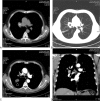

Endobronchial hamartoma mimicking malignant lung tumor contralateral endobronchial metastasis: A case report

Rationale: Endobronchial hamartoma, the most common benign lung tumor, is located in the bronchus, and it easily mimics lung cancer or bronchial metastasis. Endobronchial hamartoma can cause coughing, hemoptysis, and pulmonary infection; thus, it should be treated right away by surgery or fiberoptic bronchoscopy.

Patient concerns: We report a rare case of endobronchial hamartoma in which the clinical symptoms and imaging overlapped strongly with malignant lung tumor contralateral endobronchial metastasis.

Diagnoses: Endobronchial hamartoma coexisting with a malignant lung tumor.

Interventions: Fiberoptic bronchoscopy was conducted, and the pathologic diagnosis was hamartoma. A second fiberoptic bronchoscopy was conducted, and fine-needle aspiration cytology of the enlarged lymph nodes indicated squamous cell carcinoma.